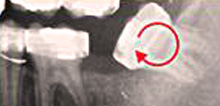

Strahlungsarmes modernstes, digitales Röntgen

Obwohl unsere Röntgentechnik mittlerweile so ausgereift ist, dass die Strahlendosis einer Aufnahme weniger als ein Fünftel der Strahlendosis während eines Transatlantikfluges ausmacht, verringern wir die Gesamtexposition indem wir so wenig Aufnahmen wie möglich anordnen, natürlich stets unter Ausblendung besonders strahlungsempfindlicher Gewebe

Obwohl unsere Röntgentechnik mittlerweile so ausgereift ist, dass die Strahlendosis einer Aufnahme weniger als ein Fünftel der Strahlendosis während eines Transatlantikfluges ausmacht, verringern wir die Gesamtexposition indem wir so wenig Aufnahmen wie möglich anordnen, natürlich stets unter Ausblendung besonders strahlungsempfindlicher Gewebe

Vorbereitung für Zahnersatz

Bei neuem Zahnersatz lässt sich oft durch enge Zusammenarbeit zwischen Kieferorthopäden und behandelnden Zahnärzten ein sowohl funktionell als auch ästhetisch optimiertes Ergebnis erreichen. Manchmal scheint es für den Zahnarzt unmöglich, einen Zahn zu erhalten, wenn dieser im Kiefer stark gekippt steht oder bis unter die Zahnfleischgrenze zerstört ist. In diesen Fällen muss der betreffende Zahn nicht entfernt werden, sondern es wird seine Stellung im Kiefer so verändert, dass er erhalten bleiben kann.

Bei neuem Zahnersatz lässt sich oft durch enge Zusammenarbeit zwischen Kieferorthopäden und behandelnden Zahnärzten ein sowohl funktionell als auch ästhetisch optimiertes Ergebnis erreichen. Manchmal scheint es für den Zahnarzt unmöglich, einen Zahn zu erhalten, wenn dieser im Kiefer stark gekippt steht oder bis unter die Zahnfleischgrenze zerstört ist. In diesen Fällen muss der betreffende Zahn nicht entfernt werden, sondern es wird seine Stellung im Kiefer so verändert, dass er erhalten bleiben kann.